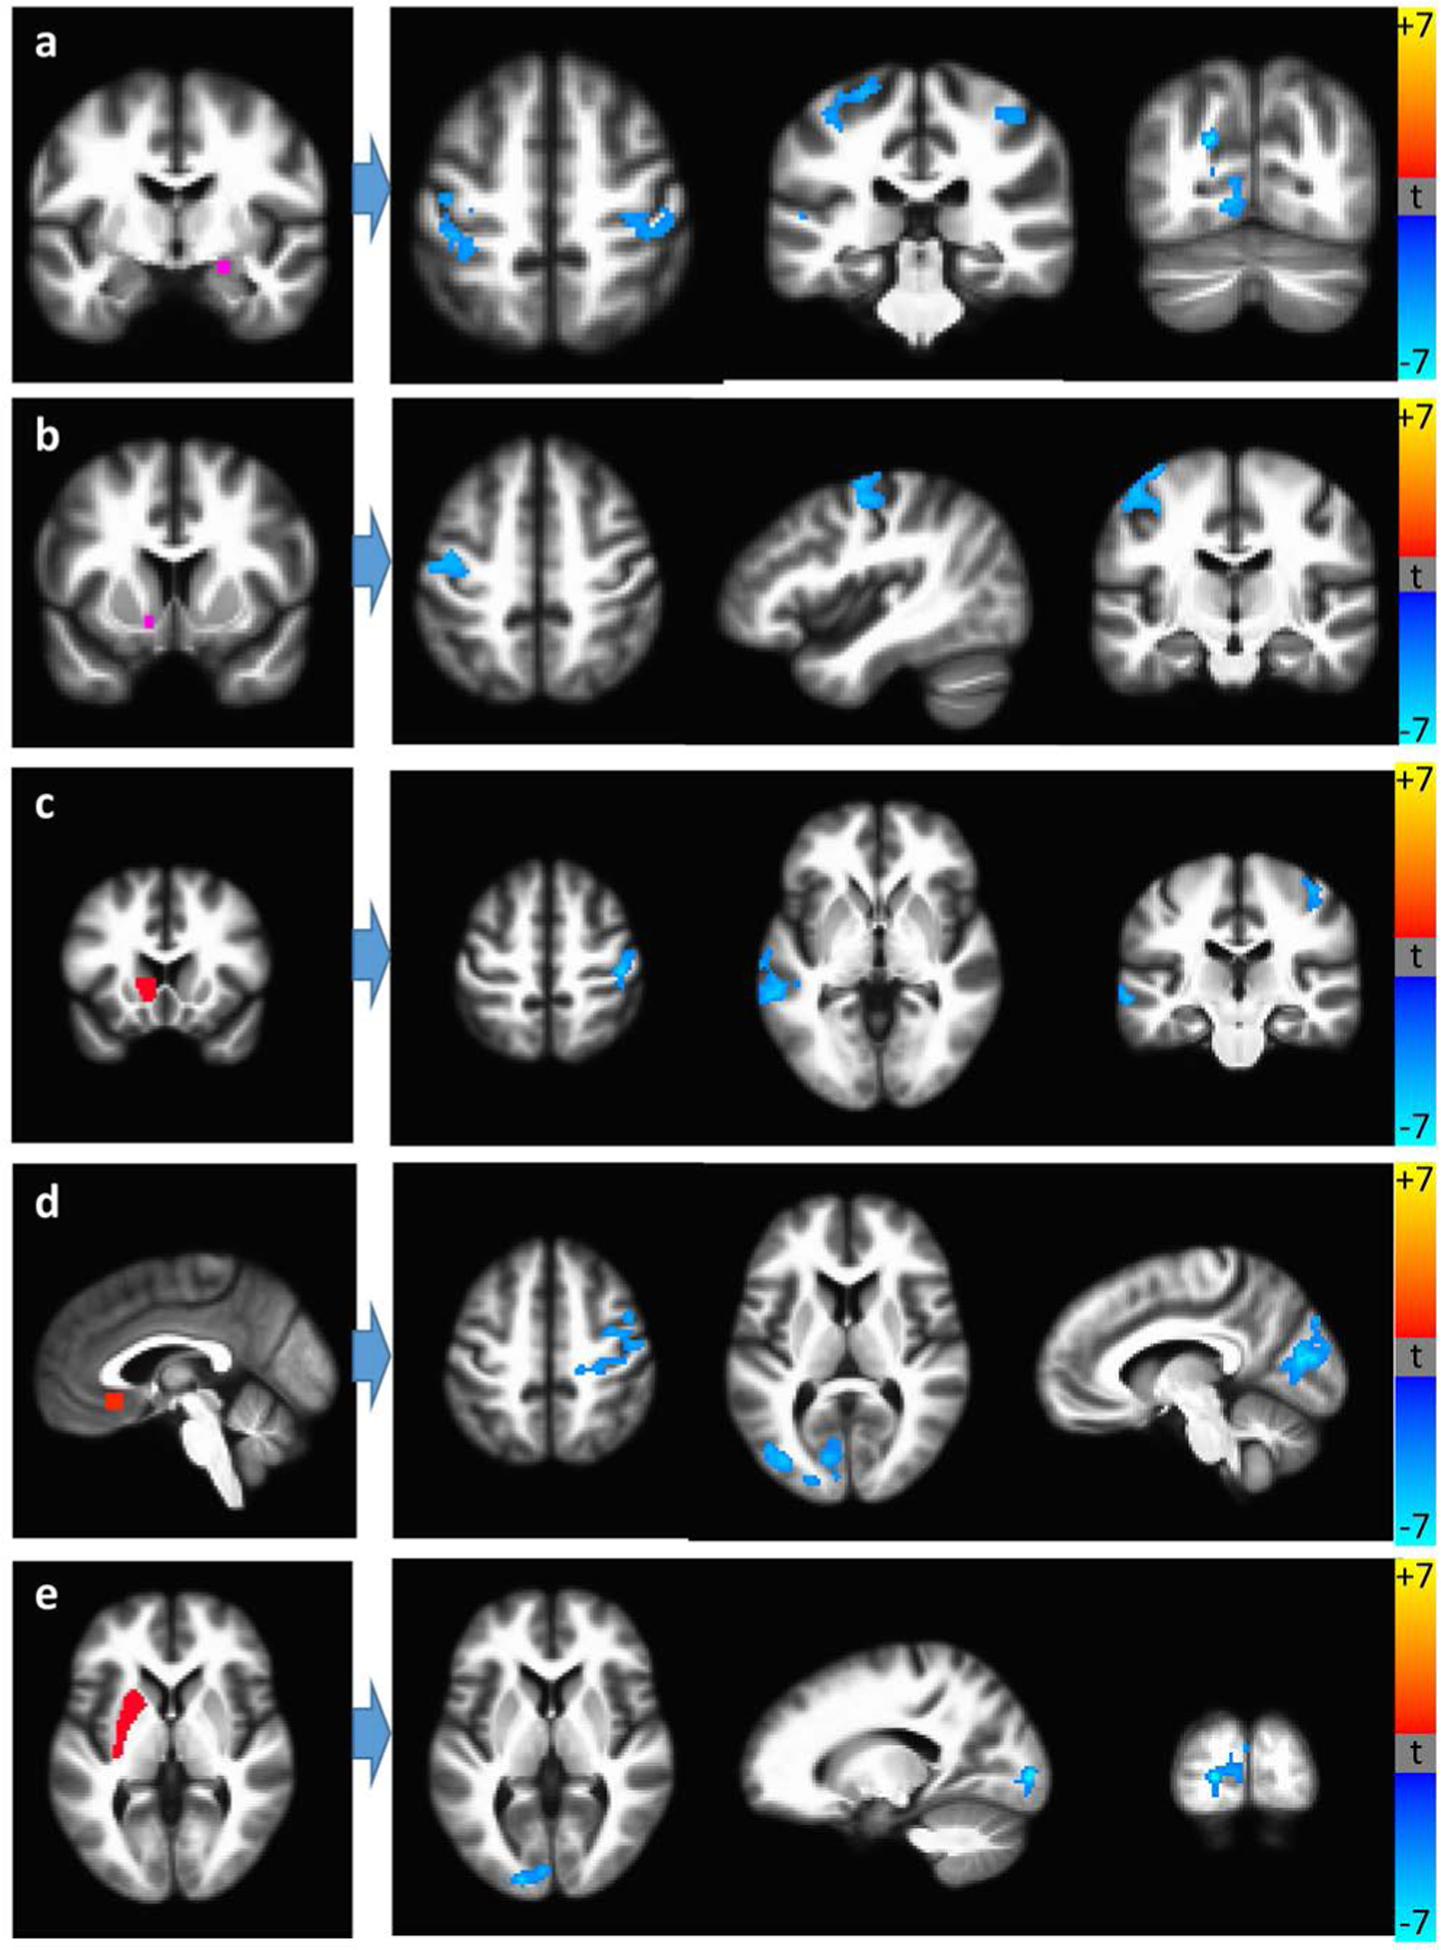

Table 4 presents significant RSFC differences between recent and remote cannabis users for the HIV+ and HIV− groups. In HIV+ participants, recent use was associated with reduced RSFC (Figure 2), including that of the occipital cortex with the amygdala, putamen and ACC. HIV+ recent users also exhibited stronger caudate-precuneus and hippocampus-motor cortex RSFC, although these results were non-significant or did not survive multiple comparison corrections. Among HIV− individuals, recent users had lower insular RSFC compared with remote users; recent use was not associated with increased RSFC.

Table 4.: Seed locations and regions showing significant RSFC differences between recent and remote cannabis users, for HIV+ and HIV− study participants (controlling for age). P-values are corrected for multiple comparisons.

| Brain region | Peak | Center-of-mass | Cluster size | p-value | ||||||||||||

|---|---|---|---|---|---|---|---|---|---|---|---|---|---|---|---|---|

| X | Y | Z | X | Y | Z | |||||||||||

| HIV-POSITIVE PARTICIPANTS | ||||||||||||||||

| Recent < remote | ||||||||||||||||

| R. Amygdala (Ce) seed | ||||||||||||||||

| L. Occipital Cortex | 12 | 44 | 0 | 14 | 62 | 6 | 437 | 0.01 | ||||||||

| L. Pre-central Gyrus | 24 | 30 | 66 | 38 | 27 | 55 | 351 | 0.03 | ||||||||

| R. Pre-central Gyrus | −36 | 26 | 58 | −42 | 24 | 57 | 287 | 0.05 | ||||||||

| L. Caudate Head seed | ||||||||||||||||

| R. Post-central Gyrus | −44 | 26 | 58 | −40 | 22 | 52 | 377 | 0.02 | ||||||||

| L. Middle Temporal Gyrus | 62 | 38 | 0 | 61 | 28 | −4 | 342 | 0.03 | ||||||||

| Subgenual ACC seed | ||||||||||||||||

| Medial Occipital Cortex | 6 | 80 | 14 | 19 | 83 | 14 | 1252 | <0.01 | ||||||||

| L. Occipital Cortex | 30 | 68 | −8 | 28 | 63 | −10 | 924 | <0.01 | ||||||||

| R. Occipital Cortex | −50 | 78 | −12 | −38 | 70 | −9 | 850 | <0.01 | ||||||||

| R. Post-central Gyrus | −28 | 26 | 48 | −40 | 18 | 52 | 548 | 0.01 | ||||||||

| L. Nucleus Accumbens seed | ||||||||||||||||

| L. Pre-central Gyrus | 44 | 8 | 60 | 43 | 15 | 58 | 334 | 0.03 | ||||||||

| L. Putamen seed | ||||||||||||||||

| Medial Occipital Cortex | 18 | 92 | 2 | 9 | 93 | 5 | 299 | 0.05 | ||||||||

| HIV-NEGATIVE PARTICIPANTS | ||||||||||||||||

| Recent < remote | ||||||||||||||||

| L. Amygdala (Ce) seed | ||||||||||||||||

| L. Middle Frontal Gyrus | −42 | 14 | 42 | −42 | 24 | 34 | 597 | 0.01 | ||||||||

| L. Caudate Body seed | ||||||||||||||||

| L. Medial PFC | −6 | 40 | 32 | −4 | 40 | 38 | 297 | 0.05 | ||||||||

| R. Caudate Body seed | ||||||||||||||||

| R. Medial PFC | 4 | 70 | 4 | 4 | 64 | 6 | 325 | 0.03 | ||||||||

| R. Caudate Head seed | ||||||||||||||||

| L. Post-central Gyrus | −60 | −20 | 36 | −58 | −24 | 34 | 463 | 0.01 | ||||||||

| R. Anterior insula seed | ||||||||||||||||

| L. Middle Temporal Gyrus | −62 | −60 | 2 | −56 | −66 | 6 | 325 | 0.03 | ||||||||

| L. Posterior Insula seed | ||||||||||||||||

| L. Superior Parietal Lobule | −18 | −52 | 68 | −28 | −52 | 62 | 520 | 0.01 | ||||||||

| R. Posterior Insula seed | ||||||||||||||||

| L. Inferior Parietal Lobule | −48 | −46 | 24 | −44 | −52 | 28 | 460 | 0.01 | ||||||||

| L. Inferior Frontal Gyrus | −42 | 22 | −14 | −40 | 30 | −14 | 377 | 0.02 | ||||||||

| L. Posterior Insula | −32 | −20 | −2 | −32 | −16 | 2 | 357 | 0.02 | ||||||||

| L. Inferior Temporal Gyrus | −42 | −6 | −38 | −46 | −6 | −34 | 304 | 0.04 | ||||||||

| Subgenual ACC seed | ||||||||||||||||

| R. Pre-central Gyrus | 54 | −4 | 50 | 46 | −6 | 50 | 1494 | <0.01 | ||||||||

| L. Putamen seed | ||||||||||||||||

| R. Inferior Parietal Lobule | 30 | −50 | 44 | 40 | −48 | 44 | 326 | 0.03 | ||||||||

CE = central nucleus of the amygdala; ACC = anterior cingulate cortex; PFC = pre-frontal cortex.